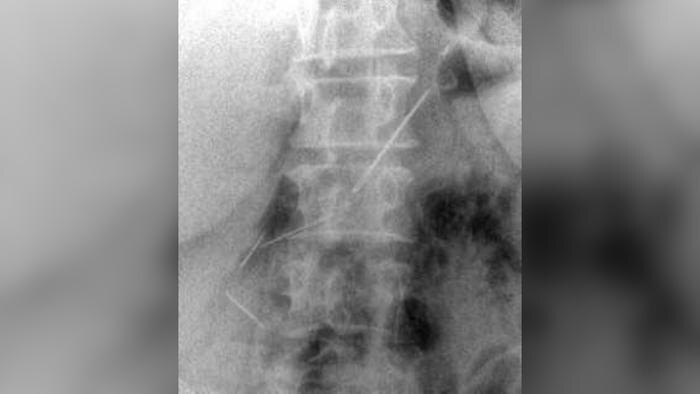

Пациентка из Красногорска полтора месяца ходила с опасным грузом в животе. Врачи достали из неё четыре швейные иглы. 59-летняя женщина обратилась в больницу с болями. Диагностика показала: три иглы в брюшной полости и одна — в передней брюшной стенке, сообщили в Минздраве Московской области.

Женщину, проглотившую четыре швейные иглы спасли в Красногорске. Фото © пресс-служба Минздрава Московской области